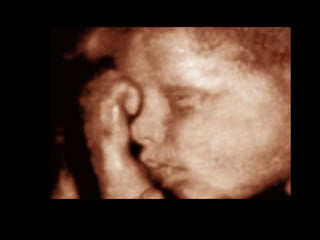

Ultrasound scan diagnosis

Ultrasound images of clefts of the lip can be visualized as

early as 16 weeks

• 15.

Ultrasound scan diagnosis Ultrasoundimages of clefts of the lip can be visualized as early as 16 weeks